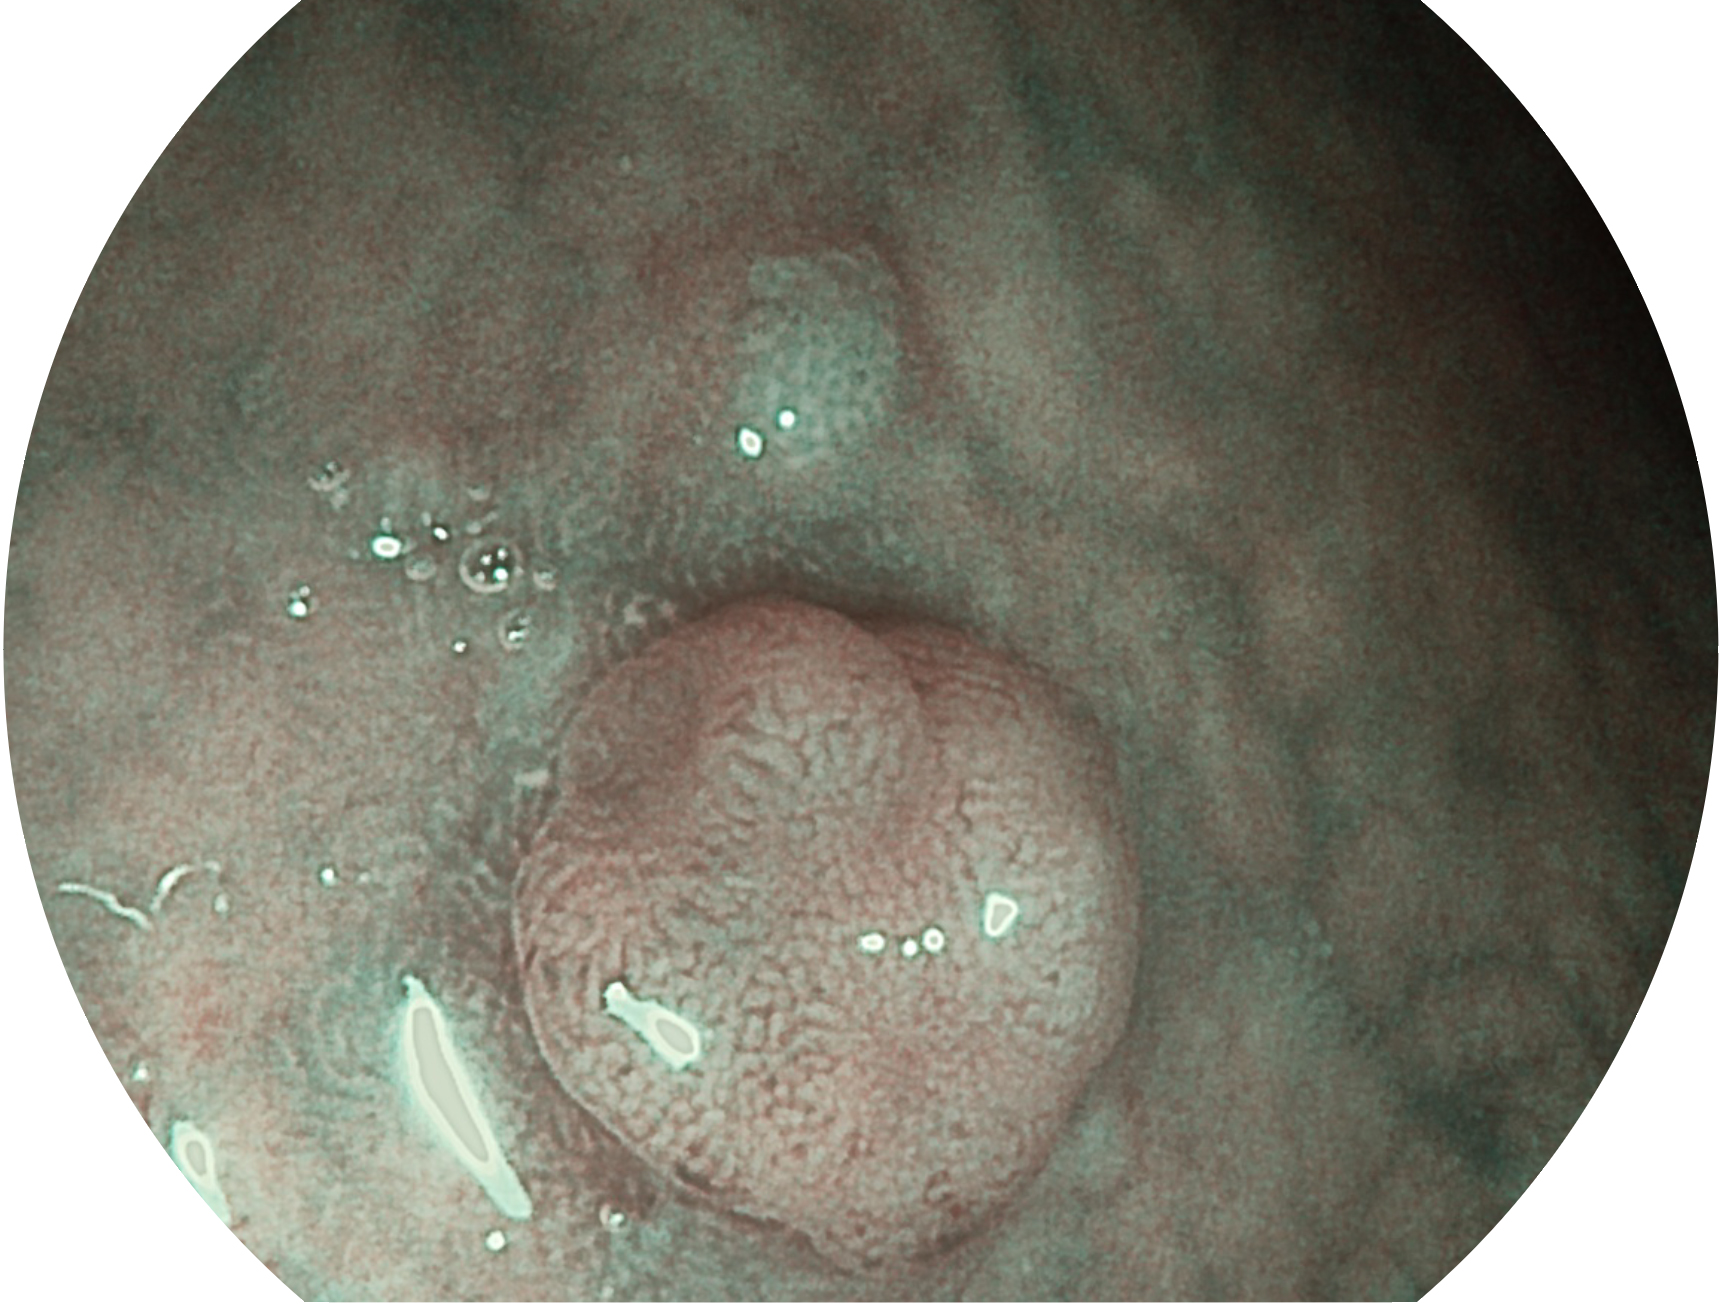

九州酷游新开发的内镜染色技术,主要是基于多波长LED 光源的开发,VLS-55Q 四波长LED 光源是由四个不同颜色的LED光按照相应照明模式所规定的特定发光比例进行合束后形成,合束后形成的照明光的光谱由红光、绿光、蓝光及蓝紫光这四个不同的波段范围构成。具有更高光谱自由度,通过光谱比例的控制,实现了聚谱成像技术,英文全称为“Spectral Focused Imaging, SFI”,缩写为“SFI”和光电复合染色成像技术,英文全称为“Versatile Intelligent Staining Technology, VIST”,缩写为“VIST”。